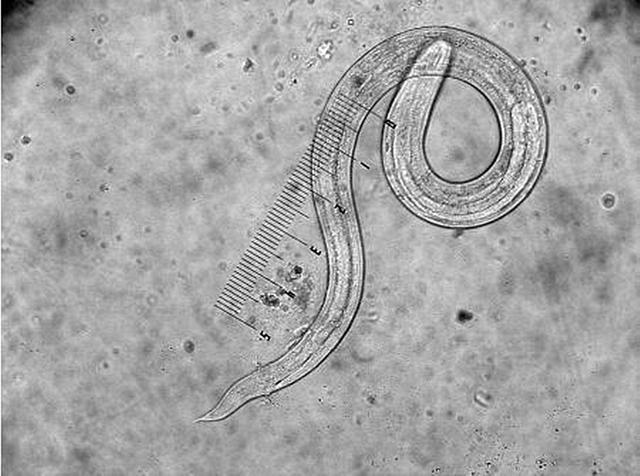

经过检查,医生在显微镜下观察大便涂片,找到了蛲虫卵,还有一条蛲虫